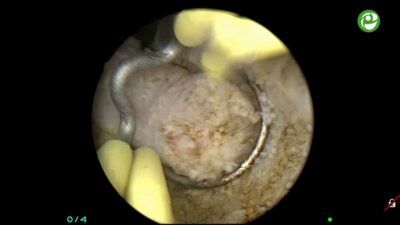

Школа по трансуретральной хирургии простаты

25 июн 2015

4339 просмотров